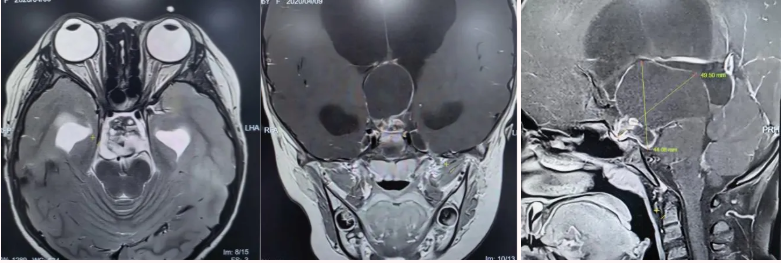

术前核磁共振检查

为精准掌握肿瘤情况,团队为欢欢完善了垂体MRI平扫+增强检查及相关激素水平检测。结果显示:肿瘤体积超过4厘米,形如鸡蛋,已严重压迫视神经与垂体,突入第三脑室,并与周围重要神经血管结构紧密粘连。颅咽管瘤是一种起源于颅底的先天性良性肿瘤,因体积大、位置深,且毗邻下丘脑、视神经、垂体等重要结构,手术切除难度极高,稍有不慎就可能导致失明、终身内分泌紊乱甚至有生命危险。